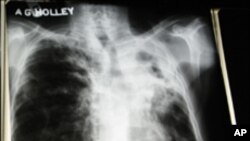

تپ دق ویکسین تجرباتی مراحل میں

عالمی ادارہ ِ صحت نے حال ہی میں ایسے69 ملکوں کی فہرست مرتب ہے جہاں ٹی بی کے ایسے مریض پائے جاتے ہیں جن پر دوا اثر نہیں کرتی۔ اس کی وجہ ایسا بیکیڑیا ہے جو انسان میں تپ ِ دق کی ادویات کے لیے مدافعت پیدا کرتا ہے۔ عالمی ادارہ ِ صحت کے مطابق دنیا بھر میں ہر سال25 ہزار افراد اس مسئلے کا شکار ہوتے ہیں۔

طبی ماہرین کہتے ہیں کہ ٹی بی کی دوا کے خلاف مریضوں میں پیدا ہونے والی قوت ِ مدافعت کی وجہ سے کسی نئی اور موثر دوا کی اہمیت ناگزیر ہو گئی ہے۔

جبکہ تب ِ دق سے بچاؤ کے لیے ویکسین کا استعمال بھی مؤثر ثابت ہو سکتا ہے۔

ڈاکٹر این گنز برگ ، ٹی بی سے متعلق ایک ادارے سے منسلک ہیں۔ اور ٹی بی سے بچاؤ کے لیے ایک ویکسین پر کام کر رہی ہیں۔ وہ کہتی ہیں کہ انہیں امید ہے کہ 2020ء تک یہ ویکسین تیار ہو جائے گی۔

ان کا کہناہے کہ ٹی بی کے لیے ویکسین کی تیاری ایک طویل اور وقت طلب مرحلہ ہے۔ اس کی وجہ اس بیماری کی پیچیدہ نوعیت ہے۔ عموما لوگوں کو ٹی بی ہو جاتی ہے اور وہ برسوں تک بیمار نہیں پڑتے ۔ اسی لیے اس کی دوا بنانے کےلیے اور لوگوں پر تجربہ کرنے کے لیے بہت وقت چاہیئے۔

بی کے لیے نئی ویکسین کا انتظار بہت طویل اور صبر آزما ثابت ہو سکتا ہے۔ عالمی ادارہ ِ صحت کا کہنا ہے کہ بہت ممکن ہے کہ ٹی بی کے مریضوں کے لیے اس سال کے آخر یا اگلے سال کے شروع تک ایک نئی اور مؤثر دوا سامنے لائی جا سکے۔